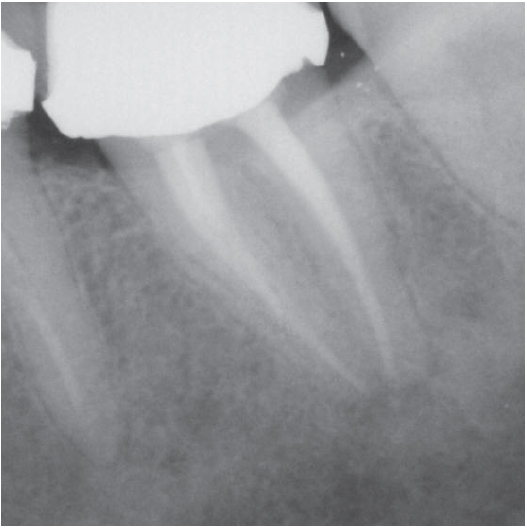

Before

Before Root Canal treatment